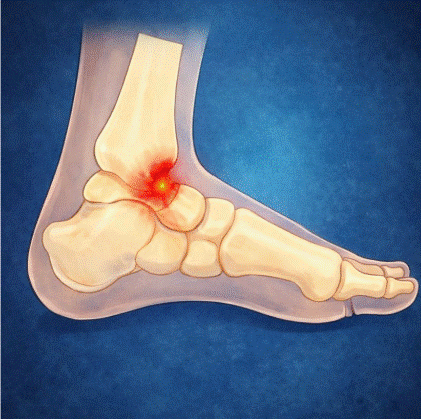

Mecanorreceptores plantares y equilibrio: plantillas y ciencia

Los mecanorreceptores plantares y equilibrio forman una relación fisiológica fundamental que durante años ha sido subestimada en la práctica clínica de la podología y la fisioterapia. La planta del pie no es simplemente una superficie de apoyo: es uno de los órganos sensoriales más ricos del cuerpo humano, con una densidad de mecanorreceptores que permite […]